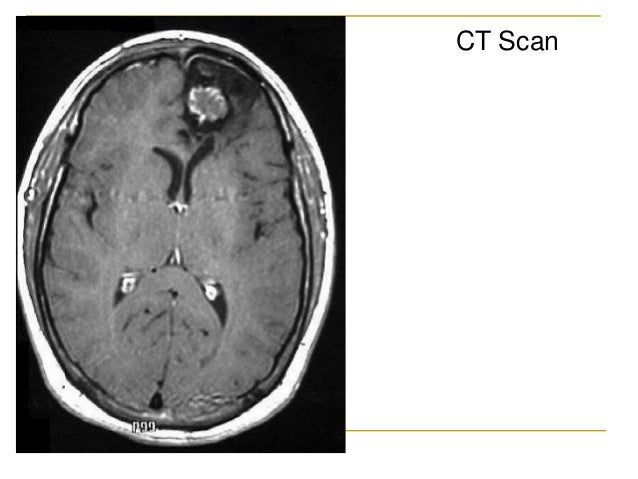

Tend to be more males than females, old. Primary brain tumors seen in dogs and cats include meningioma, glioma, choroid plexus papilloma, pituitary adenoma or adenocarcinoma, and others. I want everyone that might be going threw some of the same thing to have hope in your. Meningioma are the most common intracranial neoplasm in cats, with a frequency of around 60% of all brain tumours. Brain tumors occur more often in men than women. Examples of glial cell tumours. Brain stem tumors are heterogeneous. Tumors that form in the tissues and cells of a child's brain are called primary brain tumors. Tumors that start in the brain are called primary brain tumors. Tend to be more males than females, old. The symptoms of brain stem tumors vary greatly and can include ataxia, cranial nerve palsy, headaches, problems with speech and swallowing, hearing loss, weakness, hemiparesis. Predilections for brain tumours in dogs and cats. Stem cells in brain tumors. After taking a medical history, the doctor will examine the cat thoroughly. Brain stem glioma is usually for a focal brain stem glioma, a biopsy and removing the tumor with surgery may be considered. The brain stem, located deep in the back of the brain, is made up of the midbrain, pons, and medulla. Computed tomography (ct or cat) scan. My cat had a brain tumor. Brain tumor symptoms include headaches, nausea or vomiting, balance and walking problems, mood and personality changes, memory problems, and the most common type of primary brain tumors in children are medulloblastoma, grade i or ii astrocytoma, (or glioma) ependymoma, and brain stem. The most common indication of a brain tumor in cats is seizures, especially seizures that begin to occur after the cat has reached at least five years of age. The incidence and prevalence of spontaneous intracranial neoplasia in cats is unknown but it is commonly accepted that they are less common than dogs. Trust me he didn't pass from that it was because he got out of the house and never came back. Brain tumors in children typically come from different tissues than those affecting adults. Many brain tumors can be difficult to detect without proper testing and can display similar symptoms to ear infections or other conditions. Primary brain tumors include tumors that originate from the tissues of the brain or the brain's immediate surroundings. The brain stem is also the source of the nerves that control movement of and sensation to the face, the eyes, the throat, larynx and tongue, and the. I started some cbd for him and it helped. However, many of the times such a tumor is noticed, various treatments can be used in order to solve the problem permanently. While brain tumors in cats remain fairly uncommon, it is an issue that occurs, and that can sometimes be treated effectively. A brain tumor describes a cancerous mass within the cavity of the skull associated with the brain. Doctors diagnose brain tumors in about 85,000 people in the u.s.